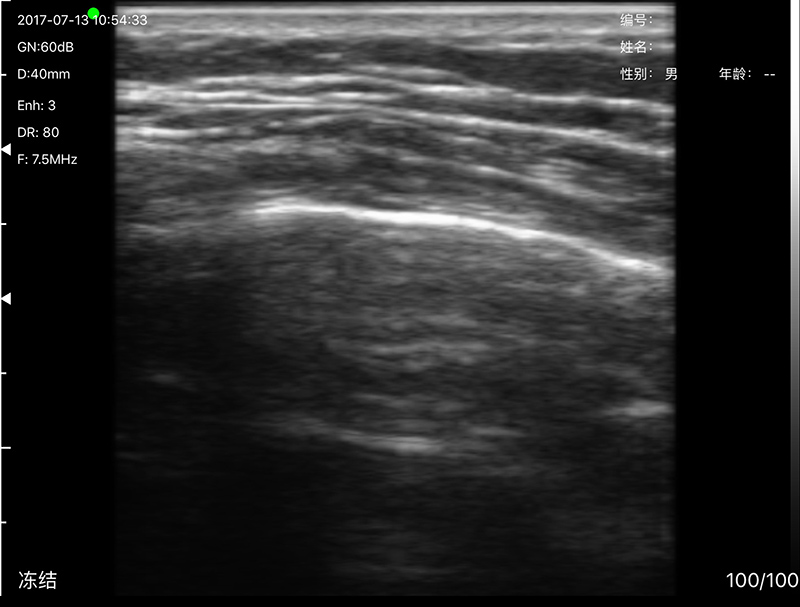

• Scan mode: Electronic Array, convex with cardiac namely phased array or linear array scanning;

• Frequency: Micro-Convex probe 5.0/7.0MHz, Linear probe 10/12MHz

• Scanning Depth: Micro-Convex 60-160mm, Linear 20-80mm, adjustable